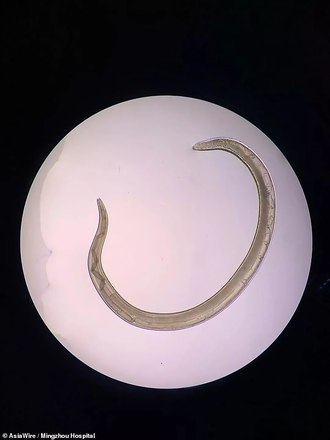

Um paciente conhecido apenas como Yan, 54 anos, passou por uma operação angustiante: a retirada de um verme do olho. Segundo o médico que fez a operação, Zhou Guping, em seu olho havia três lombrigas parasitas de cerca de 2 cm, que causaram dores agudas, que o levaram a ir fazer exames no hospital

Segundo o médico, que trabalha em um hospital da província de Zhejiang, no leste da China, trata-se da Thelazia callipaeda, um parasita que normalmente ataca cães e gatos

Para piorar, os parasitas são muito pequenos e difíceis de detectar e mais ainda de retirar em uma operação. Felizmente, os danos a longo prazo tendem a ser pequenos. "Apenas se os vermes ficarem muito tempo habitando as córneas eles podem causar lesões graves", afirmou Guping